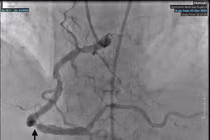

Kết quả chụp mạch vành ghi nhận tắc hoàn toàn một nhánh động mạch vành phải. Các bác sĩ đã can thiệp tái thông mạch vành và đặt stent thành công. Sau một tuần điều trị và theo dõi, bệnh nhân hồi phục tốt và được xuất viện.